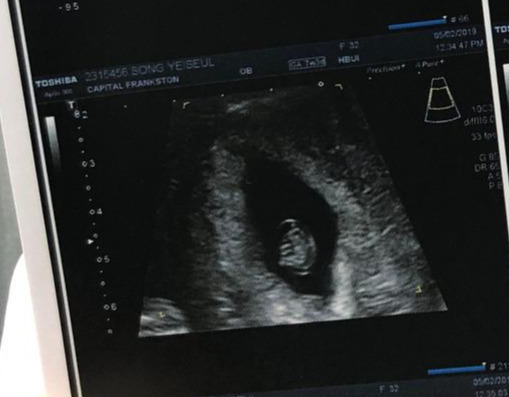

가만히 보고 있으면 처음 받아 든 초음파 사진 속 콩알 모습이 떠오른다.

두아야, 그게 네가 되었다.